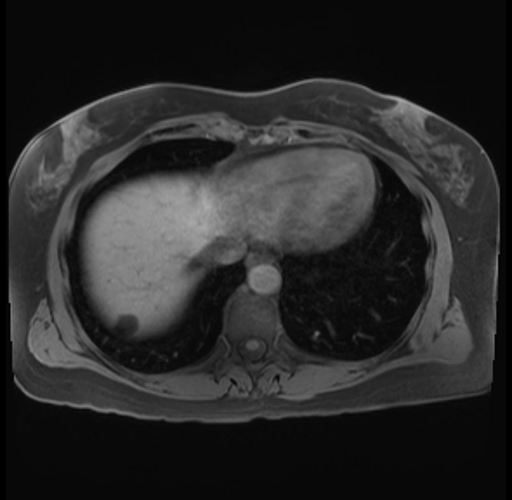

Imaging Analysis

Look through the patient's CT scan to identify any areas of concern for the necessary procedure.

Based on your CT findings, which issue(s) are present and would give reason for "planned slowing down moment(s)" in this case?

Considering a standard distal pancreatectomy procedure, what step(s) of the operation would you do differently in this case?